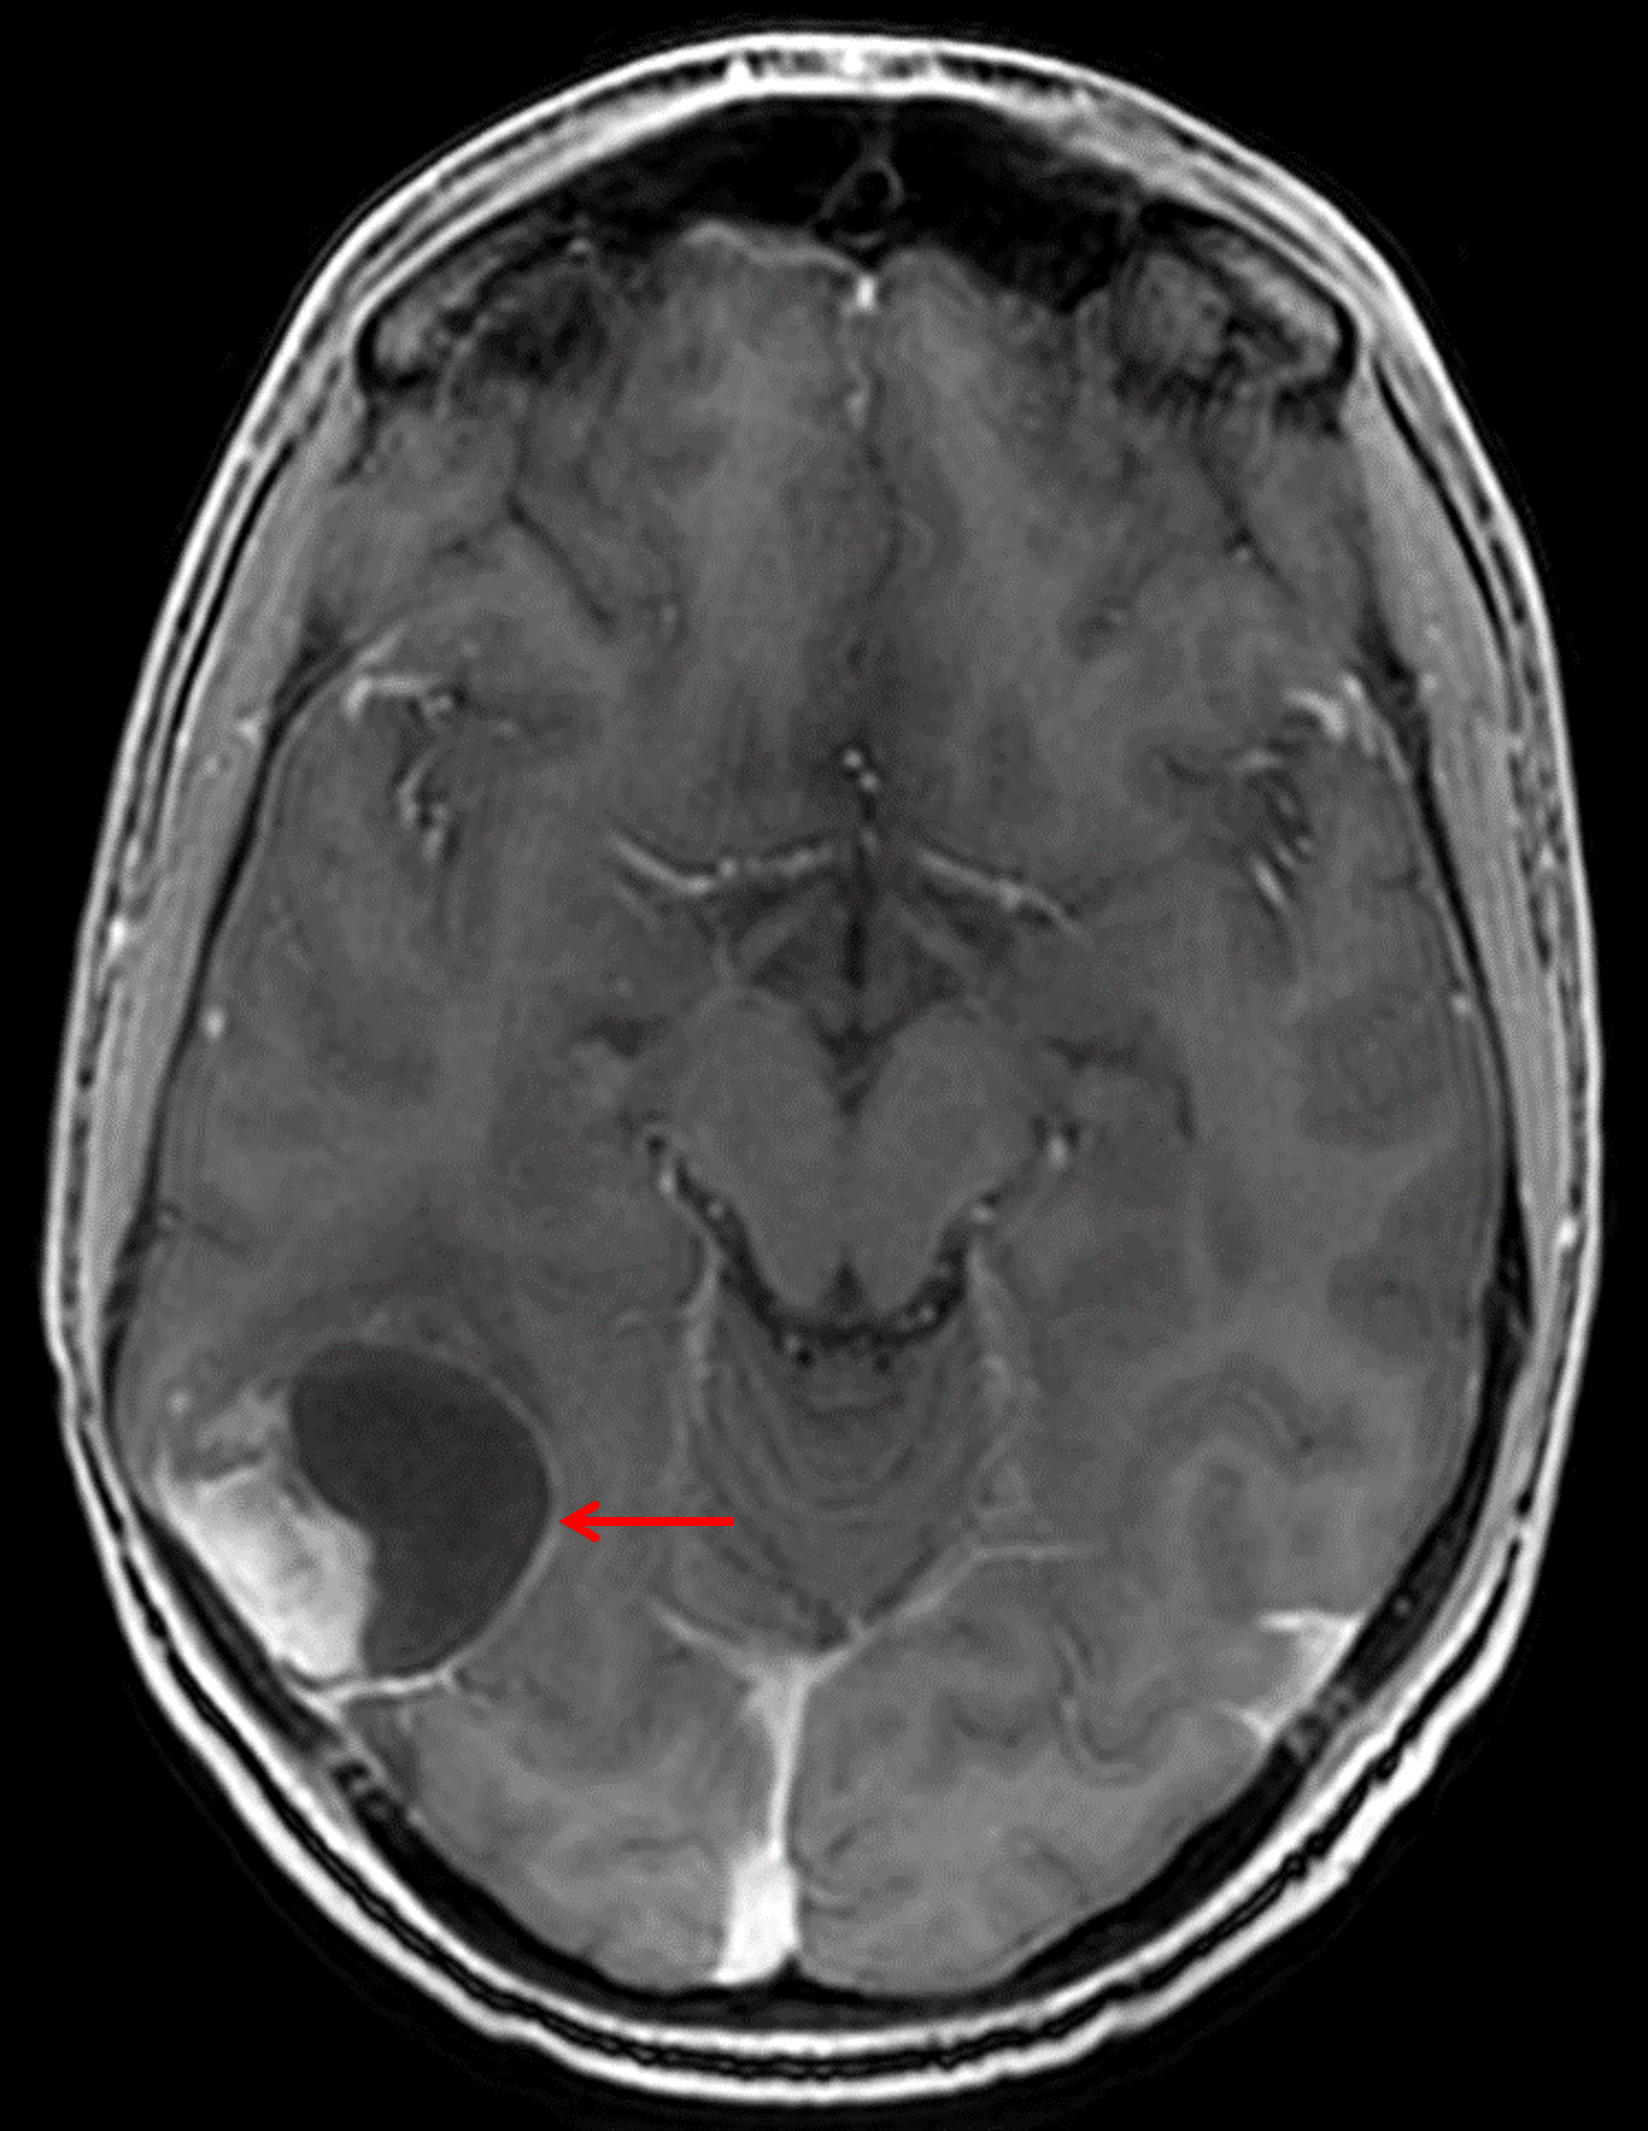

MRI

- Mixed cystic/solid mass centered in the posterior right temporal lobe measuring 4.5 x 4 x 3.7 cm

- The solid component avidly enhances and the cystic components demonstrate peripheral enhancement

- The more superior of the two dominant cystic components demonstrates relative T1 signal hyperintensity internally

- Areas of susceptibility artifact corresponding with areas of calcification on the CT

- The mass broadly contacts the overlying dura and the ependymal margin of the atrium of the right lateral ventricle, appearing to contact the choroid plexus

- Mild surrounding vasogenic edema

Mixed solid and cystic mass centered in the posterior right temporal lobe (red arrow) with adjacent broad dural contact.